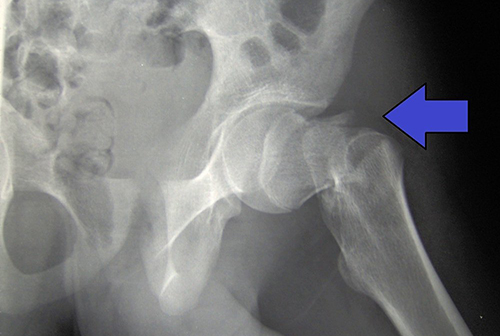

Согласно исследованию, опубликованному Journal of the American Academy of Orthopaedic Surgeons, у людей, переживших перелом бедра, в первый год наблюдается заметное ухудшение функции и самочувствия по сравнению со сверстниками без перелома.

Исследователи обнаружили, что пациенты с переломом бедра сообщили о заметном снижении частоты вождения и подвижности в первый год после перелома. В этот первый год пациенты с переломом шейки бедра реже водили машину (76% против 95% в контрольной группе), реже выходили из дома (86 против 99%), реже работали или занимались благотворительностью (17 против 44%), и большую часть времени испытывают депрессию (20% против 10%).

Однако в течение двух лет показатели мобильности и активности переживших перелом шейки бедра вернулись к уровням группы сверстников. Улучшение результатов было связано с более крупным социальным взаимодействием.